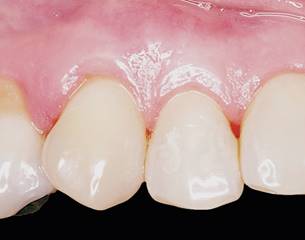

A 51-year-old female, ASA I, patient sought treatment for receding gums in teeth 1.3 and 1.2. At clinical examination, two recessions RT1 were diagnosed: one in tooth 1.3 with 2 mm. in length, and another one in tooth 1.2 with 1mm. (Fig. 4). In tooth 1.3, the PD and CAL were 1mm. and 3 mm., respectively, while in tooth 1.2 PD and CAL were 1mm. and 2 mm. (Table 1). The characteristics of the gingival margin, thickness of the gingiva and dental morphology and transparency of the probe were compatible with a thin biotype. The surgical protocol and postoperative recommendations described above for patient 1 were followed for this patient as well (Fig.5). The aim of the surgery was to increase the gingival thickness, thus developing a thick phenotype, in order to achieve complete coverage of the recession. The patient was informed of the risks and benefits and signed an informed consent.

This time, the procedure took 23 minutes. At 14 days, the tissue adhesive detached on its own. At 60 days, complete coverage of the recession was achieved. At 5 years, the gingival margins were stable. In tooth 1.3, the PD and CAL were 1mm. and 1mm., respectively, while in tooth 1.2 PD and CAL were both 1mm. (Table 1), values that remained stable over 5 years (Fig.6).